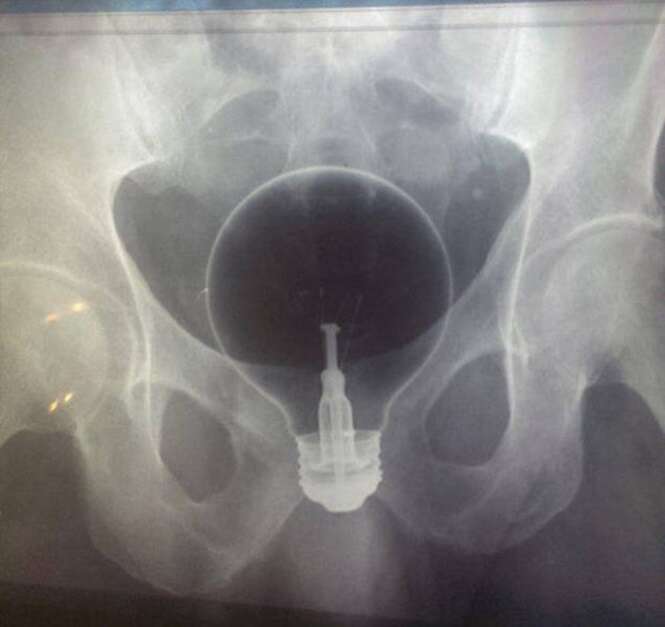

10 exames de raio-X feitos em pacientes que se deram mal tentando conseguir prazer íntimo

As imagens que você verá a seguir mostram exames de raio-X que são um tanto quanto incomuns.

Os exames mostram objetos pra lá de inusitados inseridos dentro dos corpos de pacientes de várias partes do mundo.

Todos eles certamente farão você estremecer de dor.

Os pacientes certamente tentaram usar tais itens para se dar prazer íntimo, mas acabaram se dando muito mal.